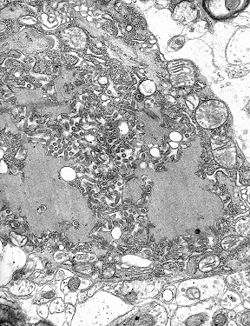

| EM of rabies virus. | |